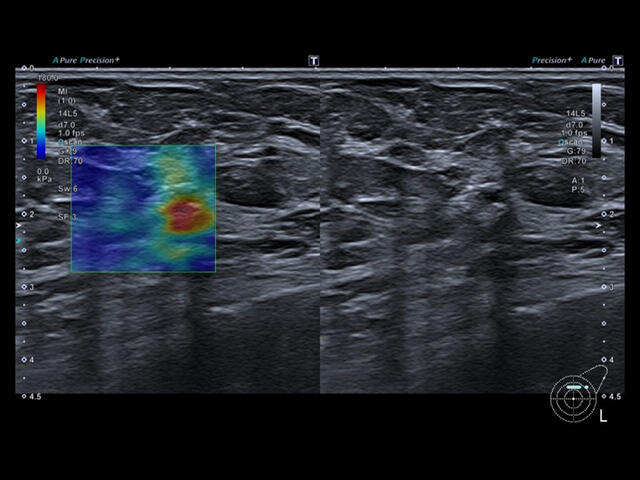

Aplio a550 может работать с линейным матричным датчиком и поддерживает новейшие монокристаллические датчики. Также Aplio a550 поддерживает большое количество дополнительных опций, таких как - SMI, Компрессионная эластография, Эластография сдвижной волны, Smart Fusion, исследования с использованием контраста (CEUS), 3D реконструкции в реальном времени (4D), функции автоматической оценки подвижности миокарда и фракции выброса.

- SMI. Опция, упрощающая визуализацию микроциркуляторного русла. С ее помощью обследуются сосуды с низкой интенсивностью кровотока, изучаются наиболее тонкие структуры. SMI упрощает диагностику новообразований, минимизирует вероятность ошибки.

- Эластография компрессионная: Elastography

- Эластография сдвиговая (эластометрия): Shear wave

Уровень сосудистой визуализации SMI в сочетании с высокой частотой кадров повышает диагностическую достоверность при оценке поражений, кист и опухолей.

SMI с цветовой кодировкой позволяет одновременно отображать информацию о потоках и оттенках серого с высокой временной и пространственной информацией.